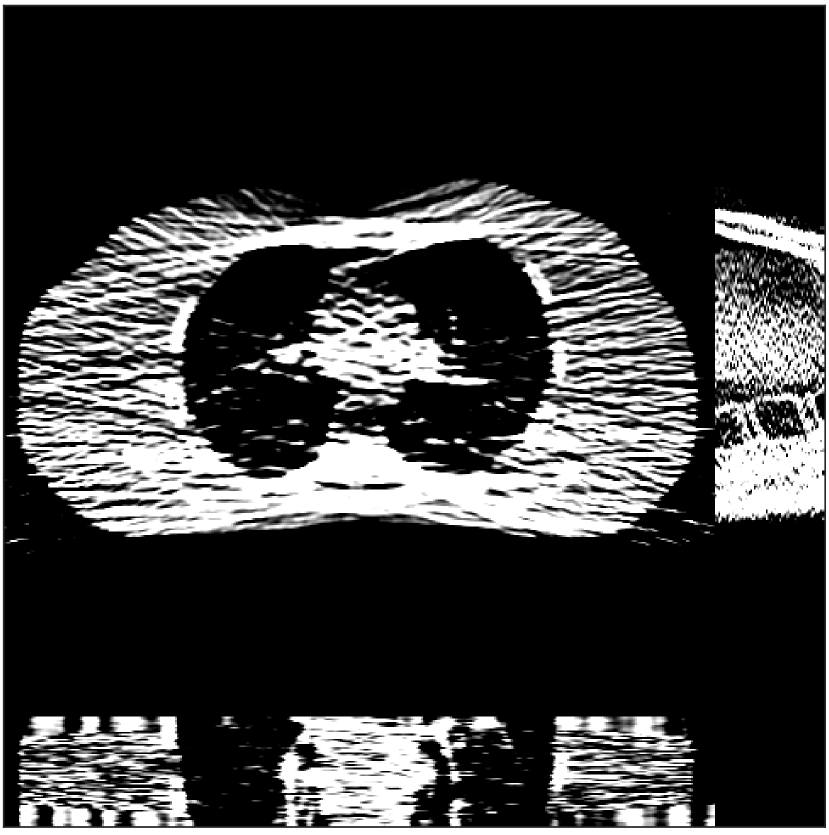

Fig. 4 shows the reconstructed images and the corresponding error images for PWLS-EP, PWLS-ULTRA, and SPULTRA, at and . Compared to the PWLS-EP result, both PWLS-ULTRA and SPULTRA achieved significant improvements in image quality in terms of sharper reconstructions of anatomical structures such as bones and soft tissues, and suppressing the noise. However, the PWLS-ULTRA method introduces bias in the reconstructions, which leads to larger reconstruction errors compared to the proposed SPULTRA method. In Fig. 4, we marked three 3D ROIs in the axial plane, i.e., ROI 1, ROI 2, and ROI 3. Fig. 5 shows the zoom-in images of a 3D plot of ROI 1, and those of ROI 2 and ROI 3 are shown in the supplement. We also plot the evolution of RMSE through the axial slices of the three 3D ROIs in Fig. 6. The figures demonstrate that SPULTRA clearly outperforms the competing PWLS-EP and PWLS-ULTRA schemes.

The above advantages of SPULTRA can be seen more clearly when observing the image profiles. Fig. 7 plots the image profiles for the three methods together with that of the ground-truth image. Fig. 4 shows the horizontal green solid line and the vertical red dashed line, whose intensities are plotted in Fig. 7. It is obvious that the profiles for SPULTRA are closest to the ground-truth among the three compared methods. The gap between the profiles of the PWLS-based methods and the ground-truth shows the bias caused by the compared PWLS methods.

Fig. 9 shows three axial slices from the 3D reconstructions with SPULTRA and PWLS-ULTRA at : the middle slice (No. 67) and two slices located farther away from the center (No. 90 and No. 120). The image profiles along a horizontal line (shown in green) in the displayed slices are also shown in Fig. 9. The reconstructed slices using PWLS-ULTRA appear darker around the center compared to the “true” clinical image and the reconstructions with SPULTRA. This means PWLS-ULTRA produces a strong bias in the reconstruction. The bias can be observed more clearly in the profile plots: the pixel intensities for the SPULTRA reconstruction better follow those of the “true” clinical image, while those for the PWLS-ULTRA reconstruction are much worse than the “true” values. Moreover, SPULTRA achieves sharper rising and failing edges compared to PWLS-ULTRA. In other words, SPULTRA also achieves better resolution than PWLS-ULTRA. Fig. 9 also shows a zoomed-in ROI for each of the chosen slices, and highlights some small details with arrows. It is clear that in addition to reducing the bias, SPULTRA reconstructs image details better than PWLS-ULTRA.